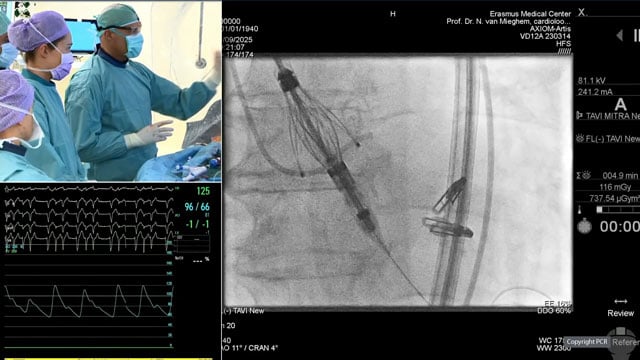

TAVI: LIVE Educational Case from St. Thomas' Hospital - London, UK

18 Nov 2025 – From PCR London Valves 2025

This educational session presents a live TAVI case from St. Thomas' Hospital in London, providing detailed insights into patient presentation, imaging analysis, operator strategy, and device selection. It includes a live procedural demonstration complemented by a recorded case from Erasmus University Medical Center in Rotterdam, offering...